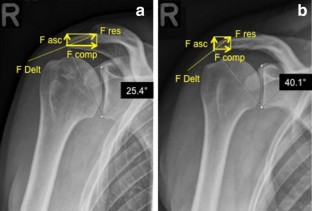

Fig. 1